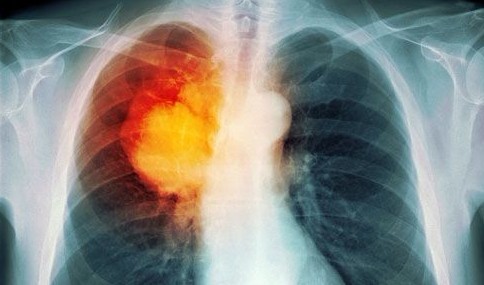

深夜,120送过来一位意识丧失、全身抽搐的老人。第一秒钟看着病床上恶液质状态的老人,我心中便有了大概的判断:要么是肿瘤晚期,要么是中风后遗症!

原来这位老人已经被确诊肺癌3个月,没有手术、化疗、放疗等治疗。3个小时前患者突然昏倒在地、全身抽搐、大便*禁失**,所以才将患者送进医院。这位肺癌老人的病情同样十分危重,肿瘤脑转移、脑水肿、重症肺炎、胸腔积液!

我同样拿着病危通知书找到家属:“1、老人的病情十分危重,随时会发生死亡!2、肺癌已经出现脑转移,所以才会导致头痛、昏迷、抽搐;同时肺部有严重的感染,和大量的胸腔积液;循环也不稳定,血压偏低、心跳较快,已经处于休克状态。3、如果愿意积极治疗的话,需要深静脉穿刺、呼吸机辅助通气,然后要住进重症监护病房里去。”